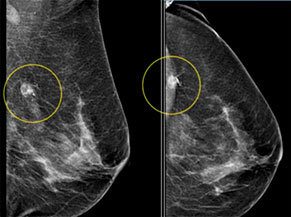

«Золотим» стандартом виявлення ранніх стадій раку молочної залози (carcinoma in situ або T<1) є самообстеження та проведення мамографії.

У центрі «Юліс» жінок навчать засобам самообстеження (огляд, пальпація) та проведуть скринінгові мамографію.

При виявленні підозрілих ділянок досвідчений мамолог проведе консультацію і оцінить необхідність проведення тонкоголкової або cor-біопсії. Результат біопсії стане відомий в той же день.